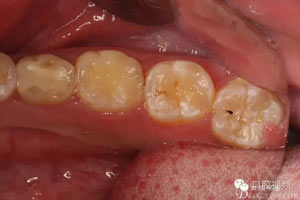

患者、盧xx、男、19歲。主訴:左側(cè)下頜乳磨牙未脫落,要求檢查。??茩z查:左側(cè)下頜第二乳磨牙有充填物。無松動,全景片檢查。35移位至36、37之間。頰舌側(cè)均不能觸及隆起。CBCT檢查:35位于36、37的舌側(cè)。表面骨質(zhì)約2mm左右。35完全骨埋伏,36的遠(yuǎn)中牙根疑是吸收。建議35暫觀察。置留不取?;颊咭蟀纬龘?dān)心壓迫36牙根或者發(fā)生囊性變。術(shù)前簽手術(shù)同意書。

圖3.術(shù)前口內(nèi)照片,舌側(cè)外形無隆起。光滑平整。